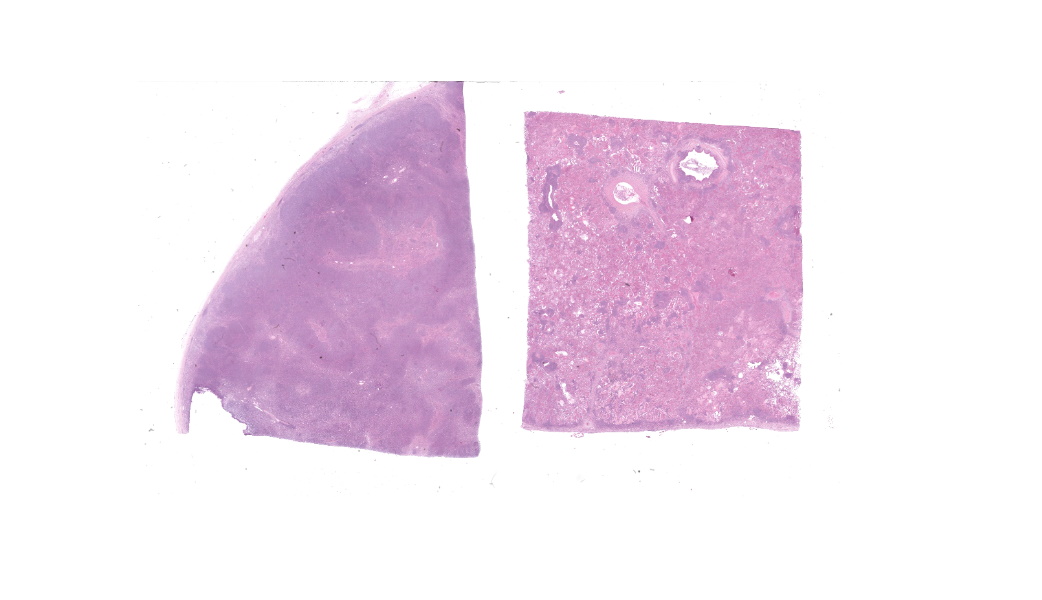

Microscopic Description:

Camel; LungDescription Multifocally throughout the section, expanding the lamina propria of larger airways, multifocally invading the airway epithelium, expanding numerous alveolar septae and infiltrating into interlobular septae and the pleural space, there is a densely cellular lymphoid neoplasm. The neoplasm is made up of sheets and rows of closely packed round cells supported by a fine pre-existing fibrous stroma. The neoplastic cells contain nuclei 5-7µm in diameter and have indistinct cytoplasmic borders, scant amphophilic cytoplasm, round to ovoid paracentral nuclei with coarsely clumped chromatin with moderate numbers of cells possessing a single nucleolus. Throughout the neoplastic cells there is mild anisokaryosis and anisocytosis. Mitotic figures numbering 5 per 2.37mm2 with occasional bizarre mitoses. Multifocally the neoplastic cells closely surround and infiltrate the tunica media of small blood vessels. Numerous alveolar spaces are filled with eosinophilic fibrillar material (fibrin) admixed with abundant neutrophils and foamy macrophages, while others contain large amounts of homogenous eosinophilic material (edema). Multifocally some alveolar spaces are expanded and ruptured (emphysema). Bronchioles contain moderate numbers of neutrophils and macrophages admixed with strands of hypereosinophilic fibrillar material (fibrin) with neutrophils transmigrating across the respiratory epithelium. There is occasional loss of type I pneumocytes with replacement by type II pneumocytes.

Camel; Paratracheal Lymph NodeDescription Multifocally the normal architecture of the cortex, paracortex and medulla is disrupted and replaced by a densely cellular neoplasm composed of lymphoid cells. The neoplasm is comprised of sheets of closely packed small round cells with nuclei 5-7µm in diameter. Cells are mostly round with indistinct cytoplasmic margins, scant basophilic or eosinophilic cytoplasm, high nuclear to cytoplasmic ratio, and a paracentric nucleus with coarsely clumped chromatin. There is mild anisocytosis and anisokaryosis. There is an average of 12 mitoses per 2.37mm2. Within the capsule of the lymph node there are small aggregates of neoplastic cells organized into sheets.

Contributor's Morphologic Diagnoses:

Lung and Lymph node; B-cell lymphomaLung; bronchopneumonia, fibrinosuppurative, multifocal, severe, subacute, with type II pneumocyte hyperplasia.